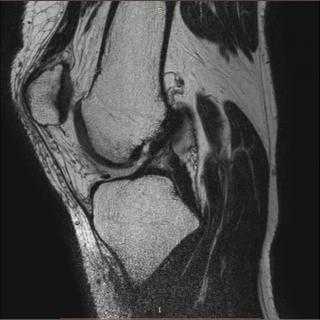

МРТ голеностопного сустава в сагиттальной плоскости. Отмечается полный разрыв пяточного сухожилия с признаками повреждения паратенона, реактивного паратендинита.